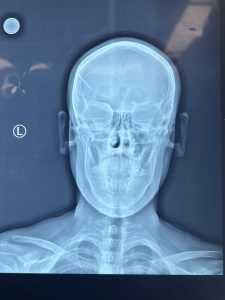

استقبلت مدينة الصدر الطبية الشاب [ م.ح ] البالغ من العمر 18 عاماً بعد تعرضه لحادث عمل مروع و إصابة بالغة في رأسه أثناء عمله كنجار نتيجة اختراق المسمار رأسه.

تم نقله على الفور إلى طوارئ الجراحية في مدينة الصدر الطبية لإجراء عملية جراحية دقيقة لإستخراج المسمار وإيقاف النزيف.

اخصائي جراحة الجملة العصبية الدكتور أحمد مطشر العبودي اكد” أن العملية كانت ناجحة وتمكن الفريق الطبي من إزالة المسمار و الخثرة الدموية وإصلاح الأغشية السحائية. وقد غادر المريض المستشفى وهو في حالة صحية جيدة.